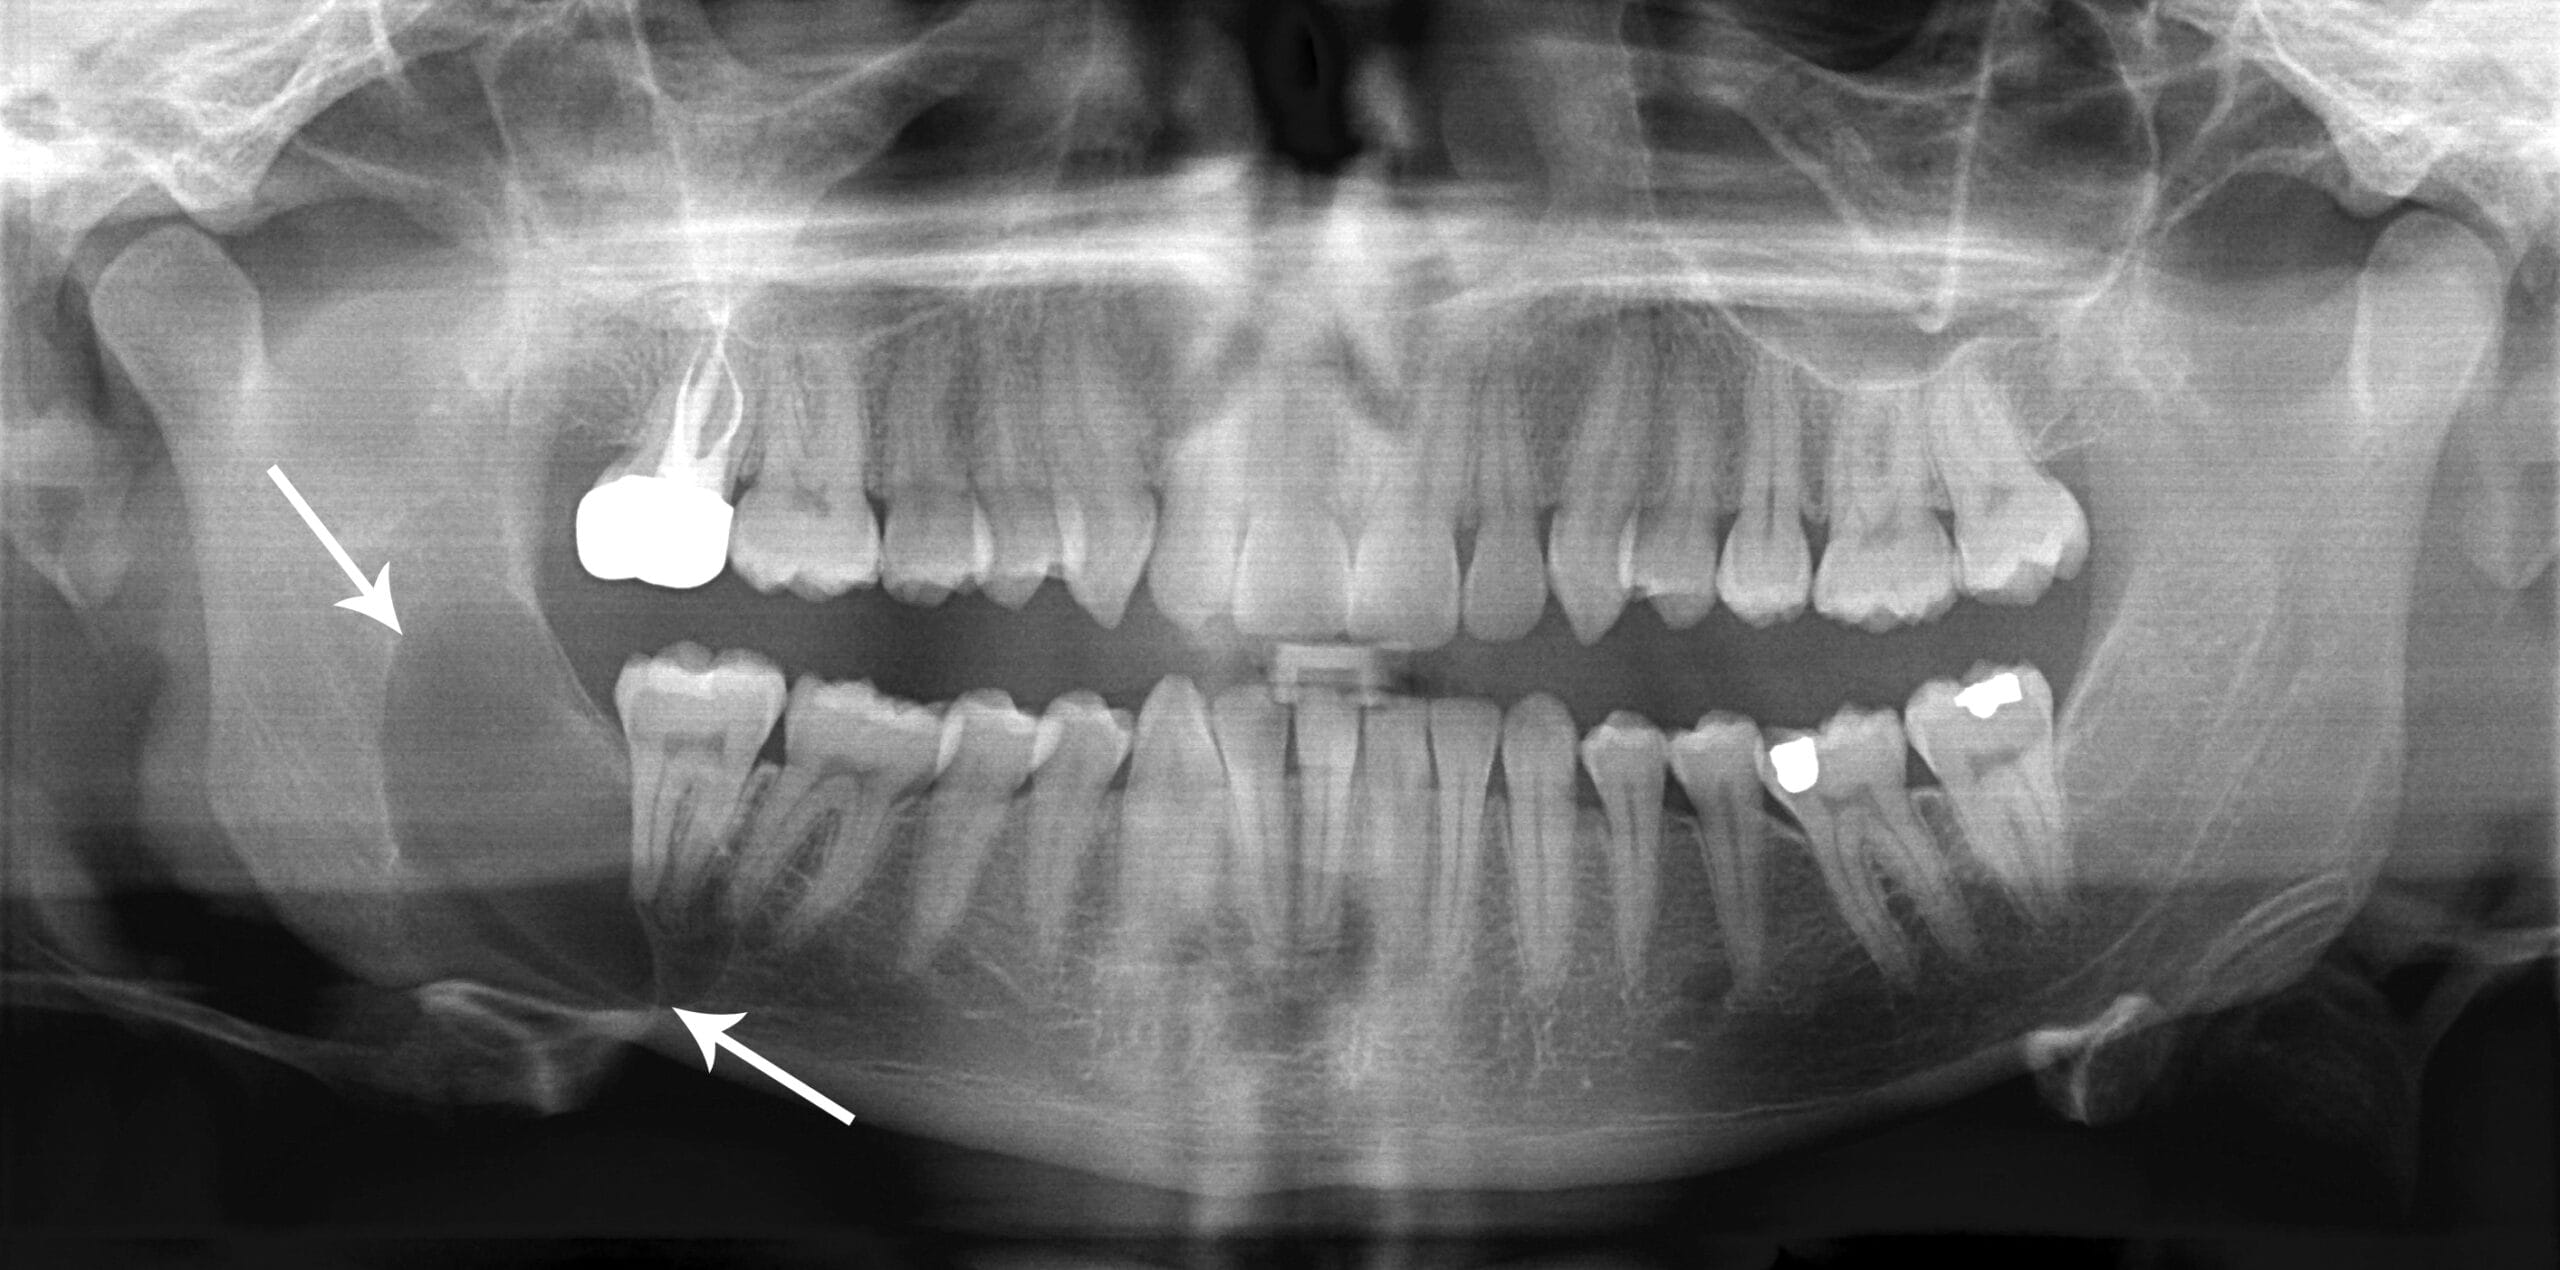

From radiopaedia.org

Wisdom tooth abscess Image Does Dental Abscess Show On X Ray An abscessed tooth can cause throbbing pain. You can't actually see a dental abscess at this stage because it is hidden within the bone. a dental abscess xray will typically show the location of the abscess, as well as the surrounding bone and any damage that may have. how we vet brands and products. plain radiograph /. Does Dental Abscess Show On X Ray.